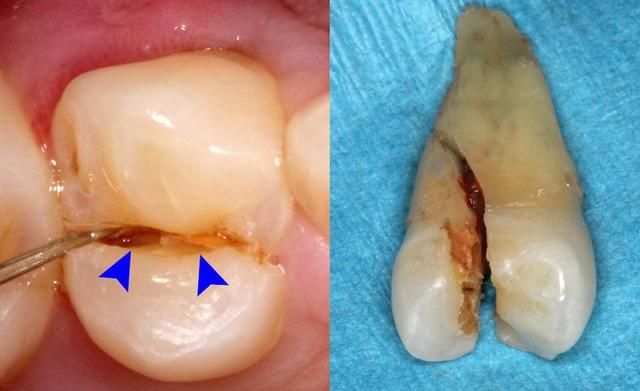

牙隱裂需要拔牙嗎

深圳牙科醫院醫生專(zhuan) 業(ye) 介紹:牙隱裂在日常生活中自己確實不容易發現,一般隻有在洗牙後,專(zhuan) 業(ye) 檢查才能看到,那麽(me) 出現這種情況是不一定需要拔牙的,還是要看具體(ti) 的牙隱裂的情況來做決(jue) 定。建議到專(zhuan) 業(ye) 口腔醫院確定是否需要拔牙。

3、如果是裂開到牙根的情況了,可能往往還會(hui) 有牙周炎症,這種情況治療後,結果也不是很理想,需要酌情處理,可能考慮需要拔牙。